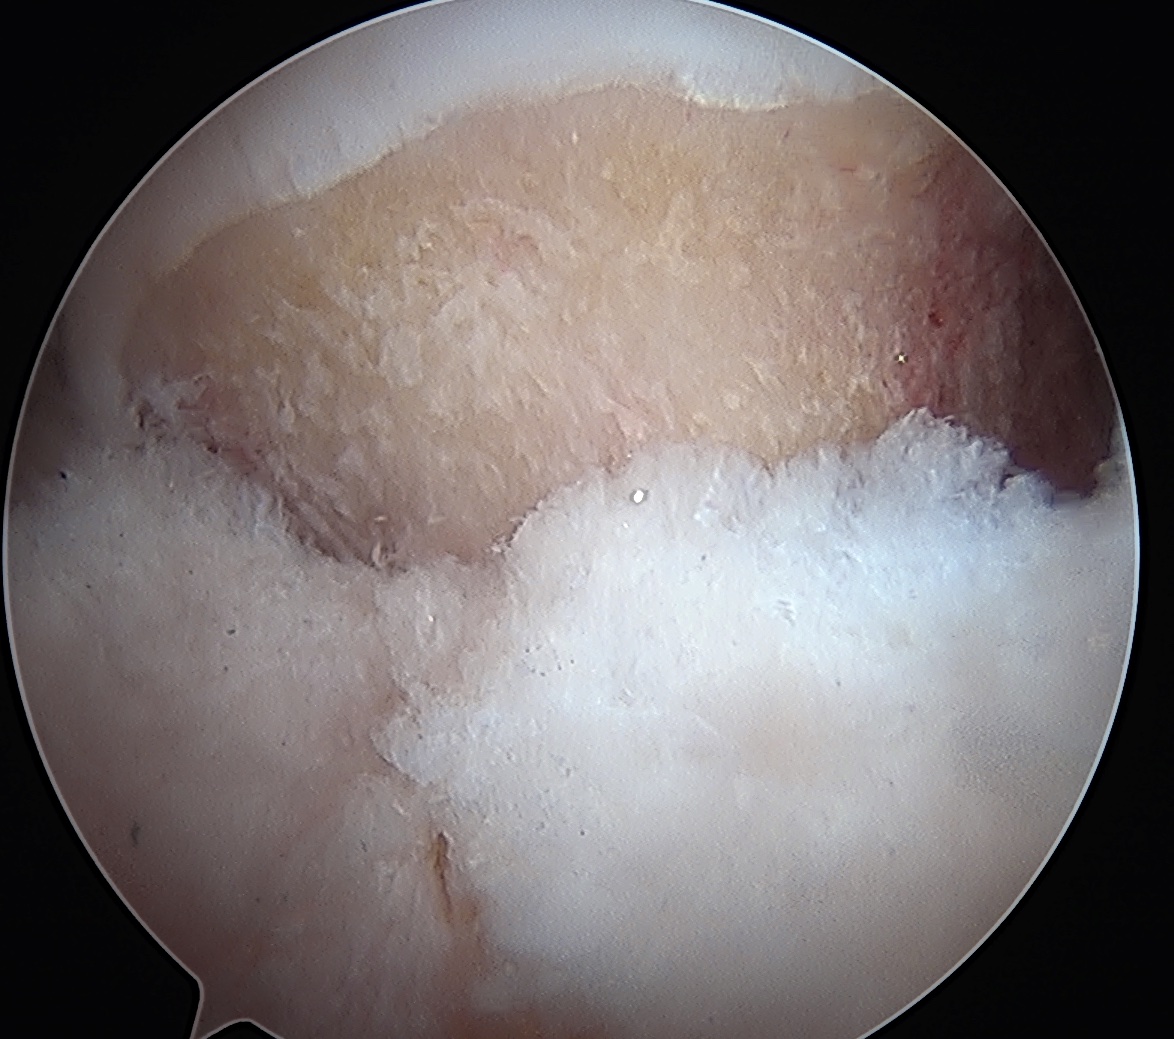

Labral Repair

Assess for Labral Tears

Labral debridement

- for degenerative / irreparable / ossified labrum / failed labral repair